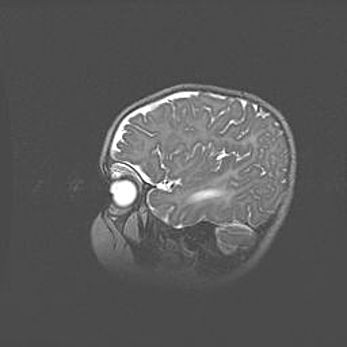

Множественные кисты обоих полушарий головного мозга, наибольшая из них в правой затылочной области. Ассиметричная атрофическая гидроцефалия.

Возраст: 7 месяцев

Вес: 5660 г

Пол: мужской

Окружность головы: 41,5 см

Срок гестации: 28-29 недель

Кисты головного мозга развиваются в результате многоочаговых некрозов вещества мозга и возникают вследствие перенесенной перинатальной инфекции, менингитов, энцефалитов, асфиксии, родовой травмы, расстройств мозгового кровообращения различного генеза. Образованию кист в веществе головного мозга плодов и новорожденных способствуют такие факторы, как высокое содержание в нем воды, недостаточная (или отсутствие) миелинизация и слабая астроглиальная реакция на повреждение.

Кисты могут сочетаться с гидроцефалией и другими поражениями головного мозга.